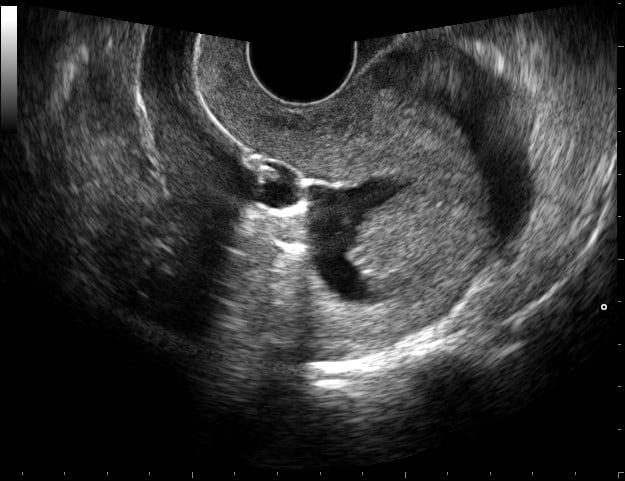

A sonohysterogram is a minimally invasive ultrasound imaging (also called “sonography”) procedure that allows a radiologist to examine the interior of the uterus and its lining (endometrium).

A sonohysterogram begins with a transvaginal ultrasound. A wand-shaped transducer is wrapped in a protective cover, coated with lubricating gel, and inserted a few inches into the vagina in order to capture uterine images. The transducer is smaller in diameter than the speculum used in a standard gynecologic exam and should not cause notable discomfort. (If it does, let the technologist know.)

After the baseline transvaginal ultrasound is completed, the transducer is withdrawn, and a speculum is inserted. The cervix is cleaned, and a thin, flexible catheter is inserted through it into the uterine cavity. The speculum is then withdrawn and the transducer reinserted for further imaging. Sterile saline is injected through the catheter in order to enlarge the uterine cavity and obtain clearer images. The entire procedure takes approximately 60 minutes to complete.